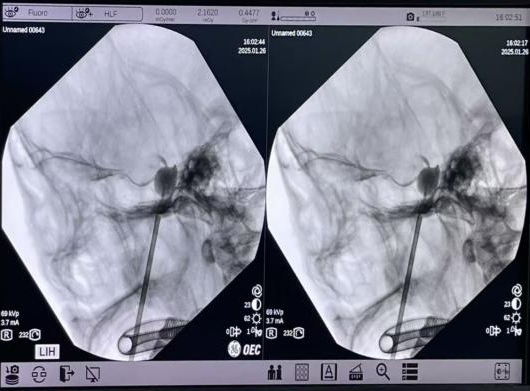

1月26日(小年夜前夕),陈龙主任医师与陆维主治医师在王文华主任医师的指导下,为靳先生实施手术。术中影像显示,球囊位置精准,创口仅为2毫米,手术过程顺利

▲术中穿刺

▲球囊释放位置精准